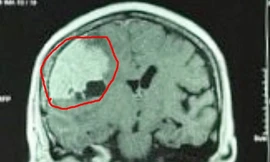

TPO - Nữ bệnh nhân nhập viện trong tình trạng mệt mỏi, đau đầu kéo dài không rõ nguyên nhân. Kết quả kiểm tra hình ảnh, bác sĩ phát hiện bệnh nhân có khối u màng não với kích thước “khổng lồ”.